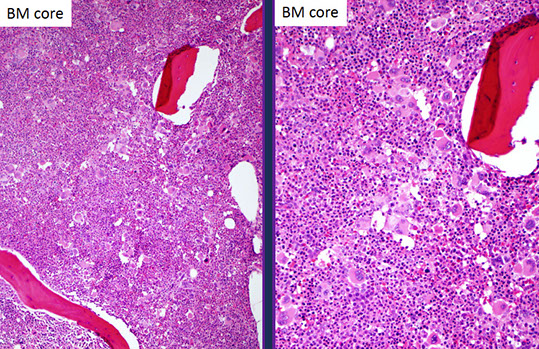

PMF

Primary Myelofibrosis

Primary Myelofibrosis (PMF)

_____________________________________

aka

(agnogenic myeloid metaplasia, AMM) (idiopathic myelofibrosis, IMF) (myelofibrosis with myeloid metaplasia, MMM) (chronic idiopathic myelofibrosis, CIM)

_____________________________________

Challenges of diagnosis PMF[2]:

- in fibrotic phases of disease, must distinguish from other causes of bone marrow fibrosis

-- close attention to morphology and mutation status (JAK2/MPL/CALR) is helpful

- in early phases of disease, fibrosis is minimal or absent

- correct diagnosis is important, since early PMF has a high risk of progression to a fibrotic disease phase and has worse prognosis than other MPNs

- morphologically distinct from ET; erythrocytosis is absent

-- increased bone marrow cellularity and more frequent, clustered megakaryocytes in early PMF compared to ET

_____________________________________

- Characterized by fibroblast proliferation, increased collagen, fibrosis, and granulocytic hyperplasia in BM; extramedullary hematopoiesis (metaplasia) in spleen and liver

- Fibrosis is a secondary reaction (mgkcs and platelets contribute to fibrosis).

- Middle aged to older people, rarely in children.

- Defective platelets (dysplastic megakaryocytopoiesis) and early cell death.

Dz assoc c JAK2 gene mutations (~50% pts) and MPL and CALR gene mutations

Anemia, abdominal pain, indigestion, fullness after eating (splenomegaly), anorexia and weight loss, fever, night sweats, lethargy and weakness.

- may look ashen; have HSmgaly, petechiae, epistaxis

Dz has long peaceful periods marked by life-threatening hemorrhagic or thrombotic events

_____________________________________

PB findings

- Mild normochromic, normocytic anemia

- Dacryocytes (cells’ tortuous circulation through enlarged spleen)

- Occasional NRBC, mild reticulocytosis.

- Giant, agranular platelets

- Rare megakaryocyte fragments.

- Occasional immature myeloid cells

- Rare myeloblasts

- Elevated serum vitamin B12 and vitamin B12 carrying capacity

- Variable (normal to increased) LAP

BM findings

“Dry tap” - no aspirate.

- Reticulin fibrosis and collagen deposition

- Hypocellularity

- Increased number of megakaryocytes

_____________________________________

Can mimic ET and PV, BMBx helps to differentiate

- morphologic features (dacryocytes in PB) can help differentiate, but are variable

_____________________________________

Dx Criteria (need all 3 major and 2 minor):

Major

1.) Mkc prolif + atypia, c fibrosis (if no fibrosis, then need hypercellular BM)

2.) No PV, BCR-ABL1 CML, MDS or other neoplasm

3.) (+) JAK2 V617F or other marker (ie MPL W515K/L)

Minor

1.) Leukoerythroblastosis 2.) Inc serum LDH 3.) Anemia 4.)S-megaly

_____________________________________

Genetics:

del(13)(q12-22) or der(6)t(1;6)(q21-23;p21.3) is very suggestive but not diagnostic of PMF

- del(20q) and partial trisomy 1q are the MC recurrent abnormalities

_____________________________________

Px

Survival from months to decades depending on the stage at first diagnosis

- worse Px in pts >70 yo, Hgb < 10, plt < 100k, and abnormal karyotype

Death from BM failure, portal HTN, thrombosis, CHF and AML

- AML may be part of the natural progression of the dz

Hemorrhage, infection, or cardiac complications are the immediate cause of death (cytoreduction and phlebotomy may help this)

- can develop fibrosis over time ("Burnt-out phase")

- 5%-8% transform into AML.

PMF advanced stage with blue collagen fibrosis, osteosclerosis

Intrasinusoidal hematopoiesis with sinus megakaryocytosis is a hallmark of this disease [2]